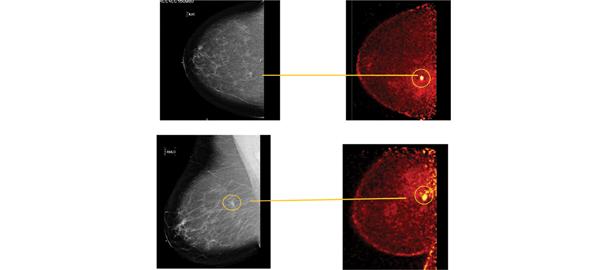

June 30, 2011 – Breast cancer screening with mammography results in a significant reduction in breast cancer mortality, according to long-term follow-up results of a large-scale Swedish trial. The results are published online in the journal Radiology.

New studies investigate effectiveness of molecular breast imaging (MBI).

Positron emission mammography (PEM), a high-resolution breast PET scanner, relies on differences in glucose metabolism to identify breast cancers from normal breast cells. Using PEM, we have an opportunity to find cancers at an even earlier stage than that detected with breast MRI, and we may even have the opportunity to find atypia because it changes cellular metabolism prior to the advent of neoangiogenesis. PEM has been shown in recently published prospective data to have similar sensitivity and superior specificity to breast MRI.

Over the years, we have seen an evolution in breast imaging. Screening mammography has been able to detect breast cancer in many women who otherwise have no signs or symptoms. Digital mammography and ultrasound are helping to better diagnose breast cancer in its earliest stages. However, no technology is perfect. Mammography sensitivity is only about 50 percent and decreases to 30 percent in women with dense breasts. Advanced technologies such as magnetic resonance imaging (MRI) are becoming more widely used for both diagnostic and screening purposes.